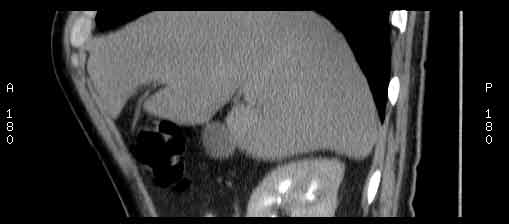

Сонограммы, КТ- артериальная, портальная и отсроченная паренхиматозная фазы

Сделали КТ (весьма похвальная тактика); по КТ: в артериальную фазу: периферическое усиление в виде сливающихся островков контраста, с центрипетальной направленностью. Венозная и отсроченная фаза-хорошее накопление контраста; образование практически изоденсно по отношению к паренхиме печени. Классика гемангиомы. Вуаля-диагноз на "тарелочке".